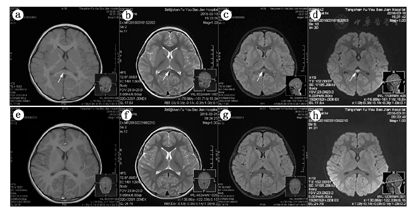

8例患儿均于起病后的第2~5天行头颅MRI增强扫描,显示SCC病变在T1加权像为等或稍低信号,T2高信号,FLAIR呈稍高信号,DWI为高信号影。在病程的第7~15天,复查头颅MRI完全恢复正常,见表2、图1。

患儿,女,4岁,因发热2 d,阵发性不能视物1 d入院,a~d于起病后的第2天,MRI显示胼胝体压部椭圆形病灶;e~h为发病后10 d复查的MRI图像,胼胝体压部病灶完全消失;a、e为T1像,b、f为T2像,c、g为FLAIR像,d、h为DWI像。